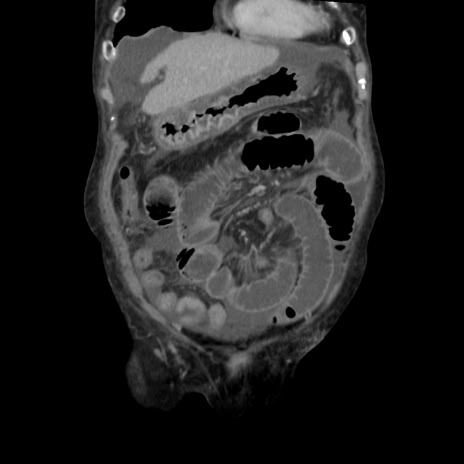

横断像

矢状断像

【症例】80歳代 女性

【主訴】腹部膨満感

【現病歴】他院にて肝硬変にてフォロー中。1週間前から便秘、腹部膨満感、臍部腫瘤あり受診となる。

【既往歴】肝硬変

【身体所見】腹部膨隆あり、皮膚変化なし、疼痛なし。

【データ】WBC 4600、CRP 0.25